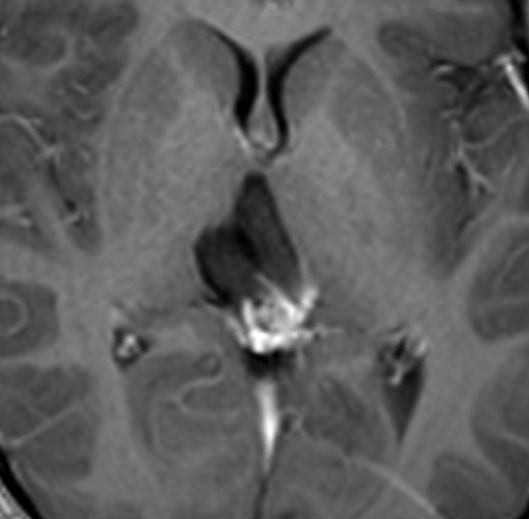

MRIです

左の拡散強調画像で高信号となり類表皮のう胞 epidermoid cyst あるいは類皮のう胞 dermoid cyst の診断です。しかし右のT2強調画像では左後方に違う信号の腫瘍塊があります。

ガドリニウム増強像です。類皮のう胞(成熟奇形腫 mature teratoma)との混合性胚細胞腫瘍を強く疑う所見です。